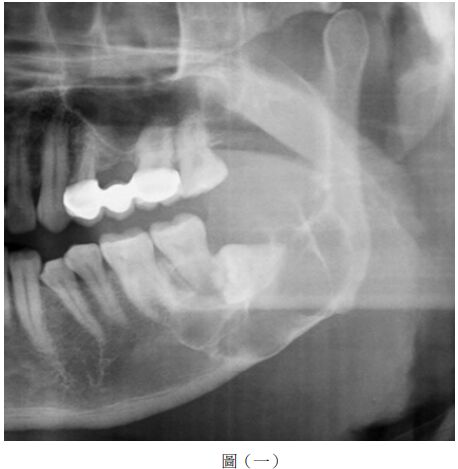

42.依據附圖,關於病人的臨床症狀或治療考量,下列何者最不可能?

(A)張口時下顎會往左邊偏移 (B)左側後牙咬合會有過早接觸(premature contact)現象 (C)會有左下嘴唇麻木(lip numbness)現象 (D)可經下顎後路徑(retromandibular approach)來進行復位及固定

44.圖中箭頭所指的骨折,下列何者正確?①favorable fracture ②unfavorable fracture ③容易錯位 ④ 不容易錯位

(A)②④ (B)①③ (C)①④ (D)②③